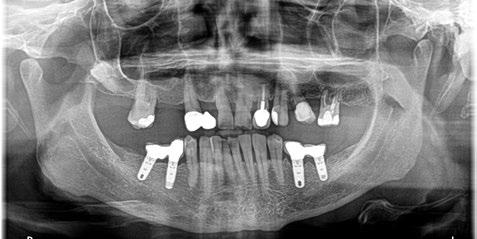

-Estudio radiográfico inicial (ortopantomografía y radiografías periapicales) (Figura 2).

Figura 2. Ortopantomografía inicial.

25, 26, 28, 37, 38, 47 y 48. Presentaba corona desajustada en 13 con extensión en 12, implantes en 35-36, 45-46, con coronas ferulizadas en 35-36, 45-46, y dientes anteriores superiores con enfermedad periodontal Grado IV.

3. Exploración de tejidos duros

En la exploración radiográfica (OPG, CBCT) observamos la existencia de pérdida ósea interproximal, lesión apical a nivel de la raíz mesial del 27 y el cordal del primer cuadrante incluido y neumatización sinusal del primer y segundo cuadrante.

En el CBCT observamos pérdida ósea posterior superior debida a la neumatización de los senos maxilares izquierdo y derecho. También podemos observar disponibilidad ósea apical suficiente en dientes antero-superiores para la realización de una Implantología inmediata y corticales vestibulares y palatinas conservadas.